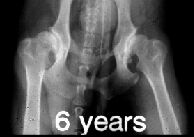

RTG snímek se provádí v tzv. extenzní ventrodorzální

projekci. Znamená to, že se psí pacient rentgenuje ve hřbetní poloze s

nataženými pánevními končetinami navzájem rovnoběžně dozadu. K

dokonalému napolohování psa se používá zvláštní lůžko ve tvaru písmene

"V" na průřezu.

Pro objektivní posouzení DKK by měl být snímek

symetrický, jelikož špatně zhotovený snímek může vést k chybné

interpretaci nálezu. Na snímku by tedy měla být zachycena celá pánev,

kost křížová a obě stehenní kosti včetně kolenních kloubů, pouze u

velkých a obřích plemen je dovoleno posunout pánev tak, že na snímku

nejsou vidět obě pately (čéšky). Stehenní kosti by měly probíhat

rovnoběžně mezi sebou a součastně s podélnou osou těla.

ŠPATNĚ PROVEDENÝ RTG SNÍMEK!!

Projekce není symetrická - stehenní kosti a podélná

osa těla nejsou rovnoběžné. |

Na levém snímku můžeme vidět kyčelní klouby zdravého

zvířete, ale na druhém snímku je zrentgenované zvíře postižené těžkou

dysplazií.